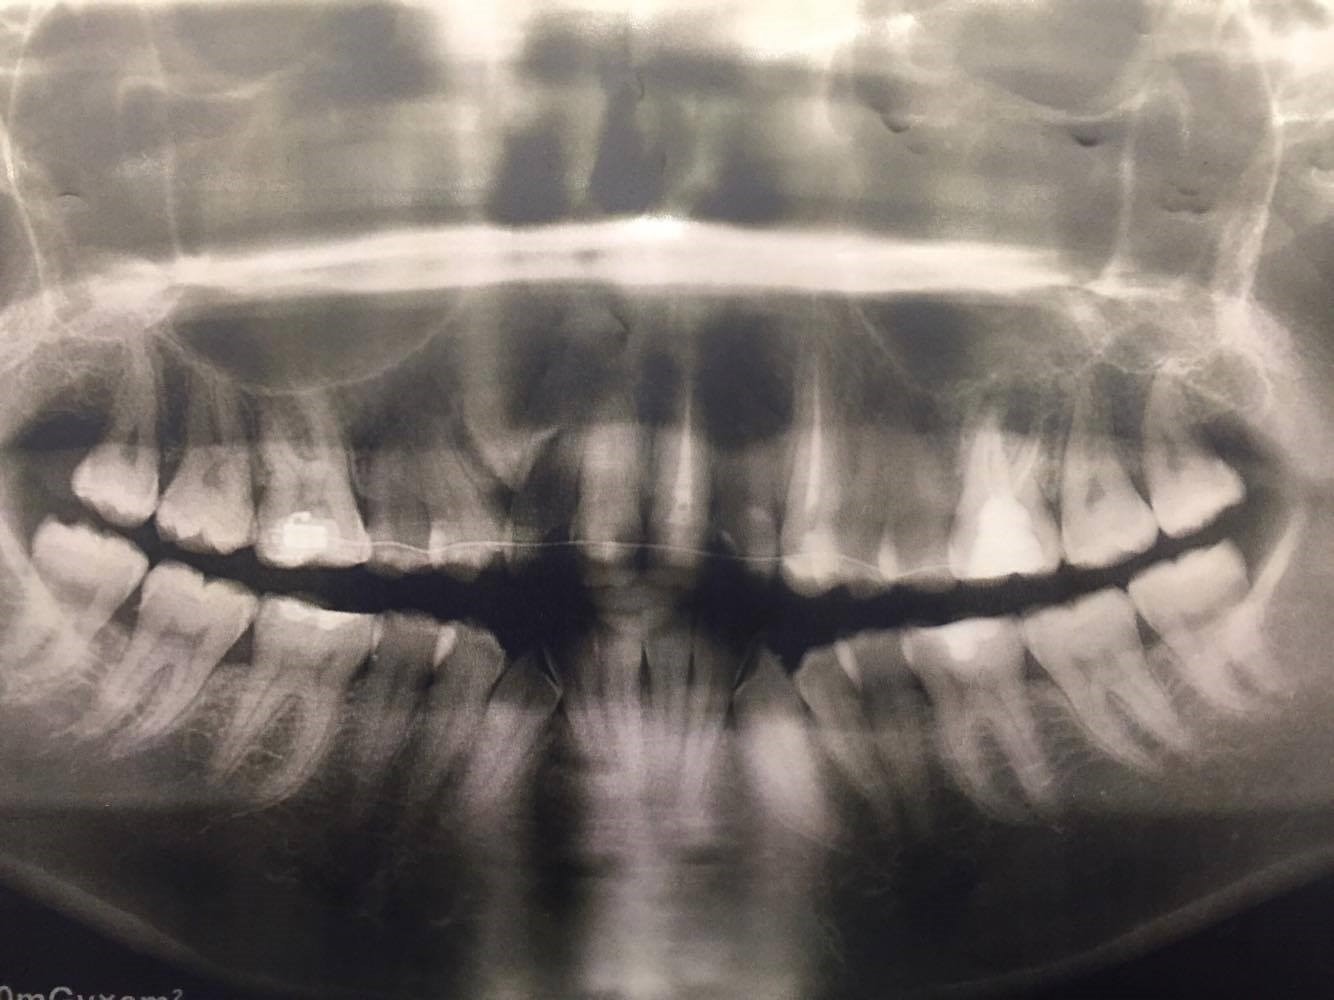

Removing the retinascent canine

The retinued fang of a young patient was removed.